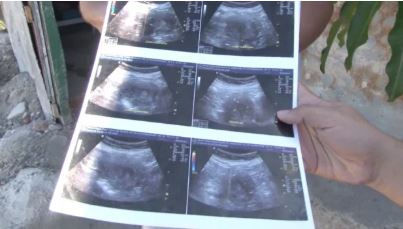

Maria de la Luz, from Mazatlan, Sinaloa, Mexico, believes she is six months pregnant with a baby girl and says she has the ultrasounds to prove it.

Speaking of the ultrasounds de la Luz said: ‘They told me it is a girl. Look, you can see her little face.’

Maria de la Luz's ultra scan